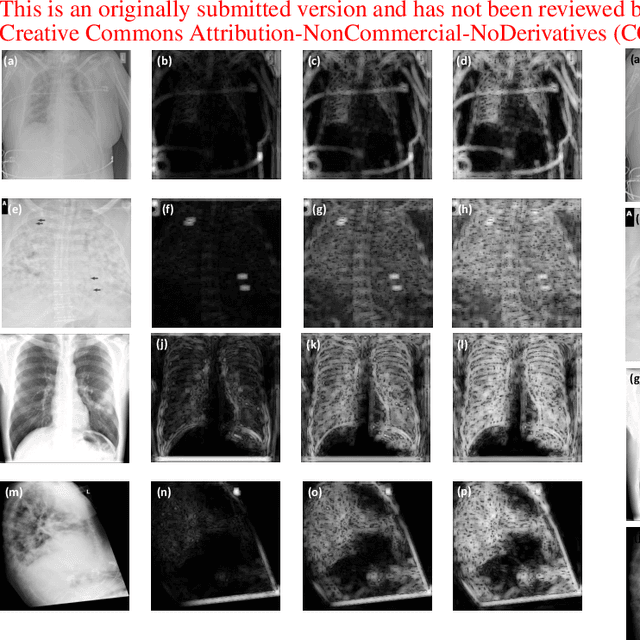

Digital radiography (DR) is becoming popular for the point of care imaging in the recent past. To reduce the radiation exposure, controlled radiation based on as low as reasonably achievable (ALARA) principle is employed and this results in low contrast images. To address this issue, post-processing algorithms such as the Multiscale Image Contrast Amplification (MUSICA) algorithm can be used to enhance the contrast of DR images even with a low radiation dose. In this study, a modification of the MUSICA algorithm is investigated to determine the potential for further contrast improvement specifically for DR images. The conclusion is that combining log compression and its inverse at the appropriate stage with a multi-stage MUSICA and denoising is very promising. The proposed method resulted in an average of 66.5 % increase in the mean contrast-to-noise ratio (CNR) for the test images considered.